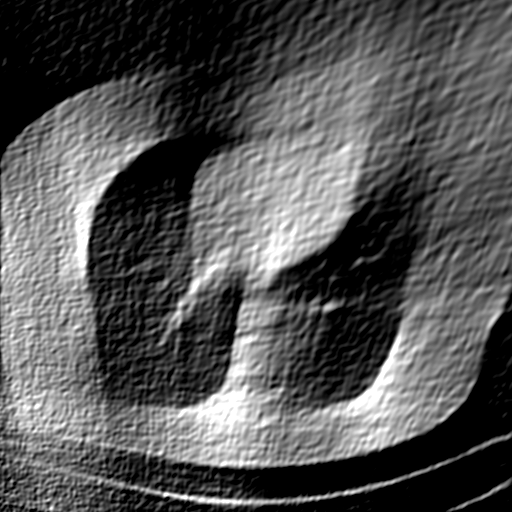

We further increase the noise level contained in the raw data to 10% white Gaussian noises and list the quantitative results in Table IV. It can be observed that the reconstruction performance of the TV model is poor in the case of high-level noises with PSNR dropping by 4 to 5 dB compared to the previous experiments. On the other hand, the performance of the learning-based methods is less sensitive to noises. The SIPID method relying on the sinogram interpolation works better than FBP-Unet. And the deep unrolling methods (i.e., PD-net, IFSR-net, SFSR-net) outperform the traditional iterative algorithm when the scanning range is limited and data is corrupted by noises. Similar to the previous experiments, compared with other deep learning algorithms, our LRIP-nets give the reconstruction results with higher PSNR and SSIM. Moreover, the low-resolution image obtained by the projection data down-sampled with rate 1/8 always gives the best reconstruction results with more than 2 dB PSNR and 0.05 SSIM increments compared to the PD-net. Fig. 6 illustrates the reconstructed images from different methodologies with scanning angular range of and 10% Gaussian noises. It can be seen that the both TV model and the FBP-Unet suffers from significant artifacts, which present distortions in the angular range of the missing scan. Other learning-based methods provides better visual qualities than FBP-Unet, and our LRIP-net1/8 still gives the best reconstruction result with correct boundaries and fine structures.

Fig. 7 manifests the reconstruction results of these methods with scanning angular of . It can be seen that both FBP and FBP-Unet produce serious artifacts within the range of missing angles. The TV model performs well in removing Poisson noises, but it can not handle the artifacts very well. Similarly, there left obvious artifacts on boundaries and different degrees of missing in visceral tissues of the reconstruction images obtained by the SIPID, PD-net and FSR-net. The visceral tissue and boundaries of our LRIP-net reconstructions are more intact and smoother, especially for the LRIP-net1/8 which gives the ideal boundaries. The observation becomes even apparent if we look at the zoom-in regions, where the LRIP-nets can produce results with fine structures. Therefore, we conclude that the low-resolution image prior can effectively improve the qualities of the limited-angle CT reconstruction.